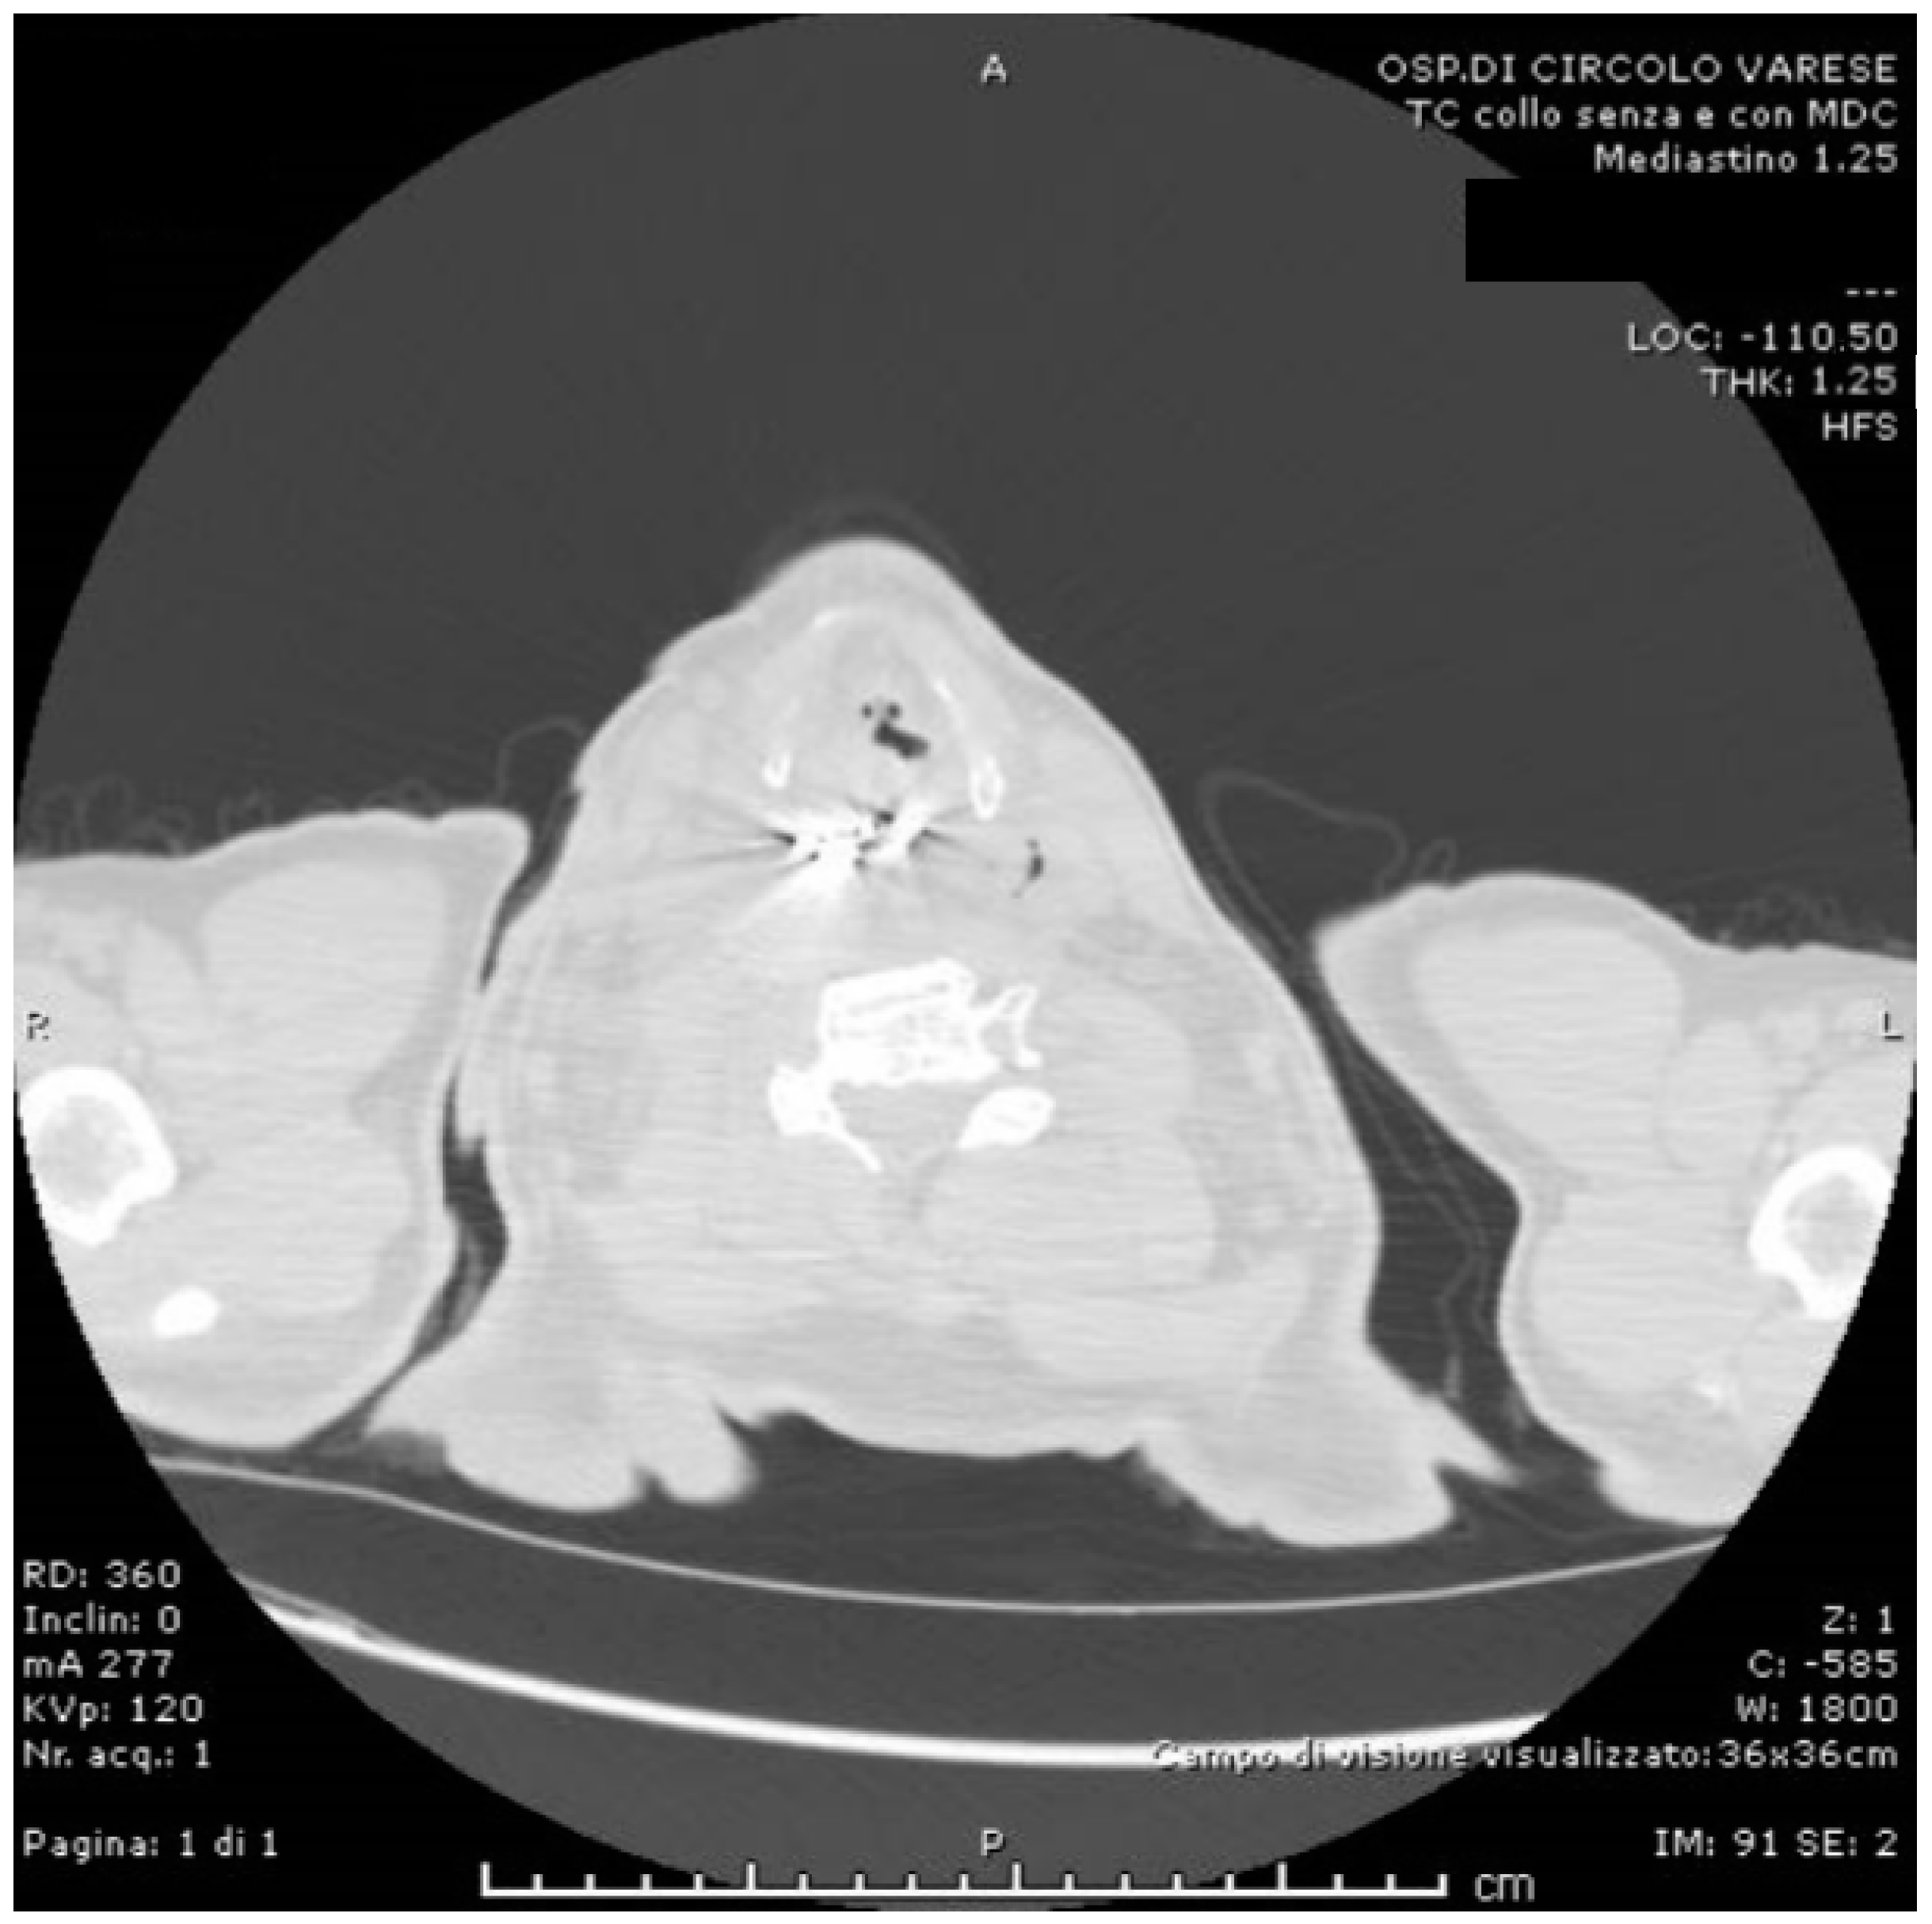

2. Case Presentation